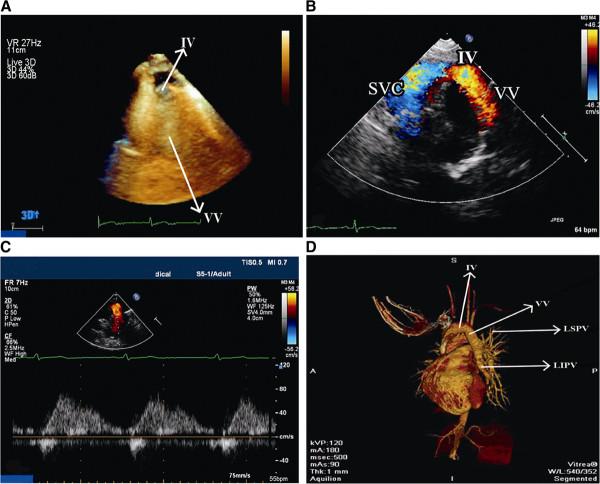

Multiple anomalous left pulmonary venous connections detected with transthoracic echocardiography.

Partial anomalous pulmonary venous connection is a rare congenital anomaly in which one or more pulmonary veins are connected to the venous circulation. The condition is frequently misdiagnosed, and usually identified by transesophageal echocardiography or invasive cardiac catheterization. We present the case of a 26-year-old female with new onset dyspnea on exertion who was diagnosed with the left superior and inferior pulmonary veins draining into the innominate vein via a vertical vein by two and three-dimensional transthoracic echocardiography and multidetector computed tomographic angiography.